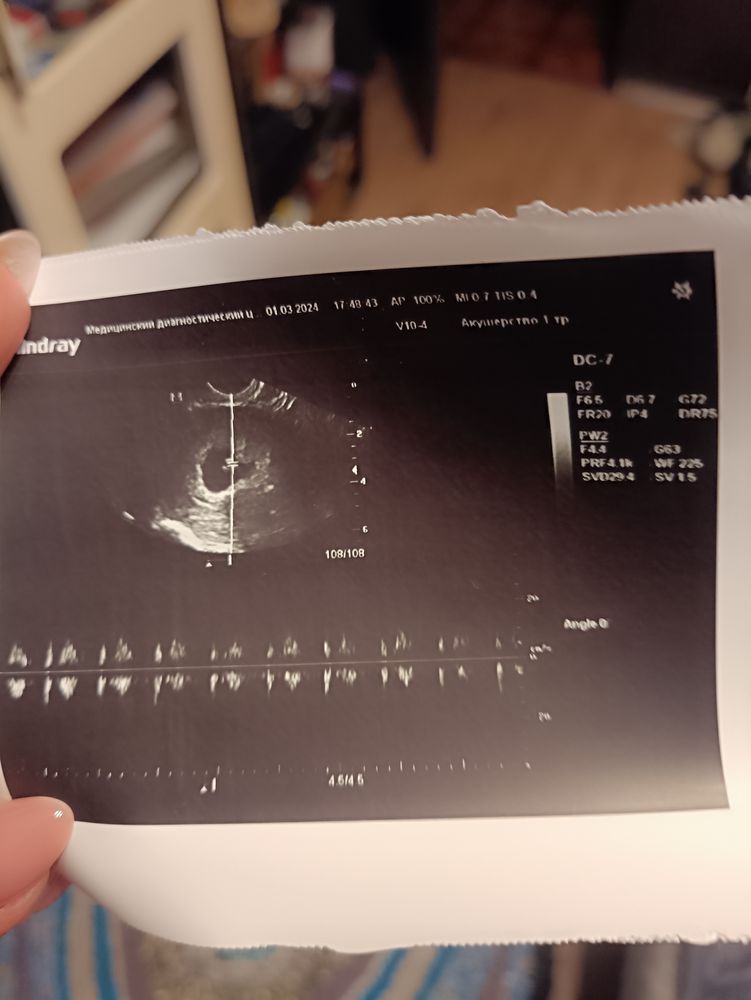

Все есть) я самая счастливая) СБ+ слушала его и плакала) чсс 152

Увидела эмбриончик, ктр соответствует 6 нед 6 дней, что соответствует сроку.